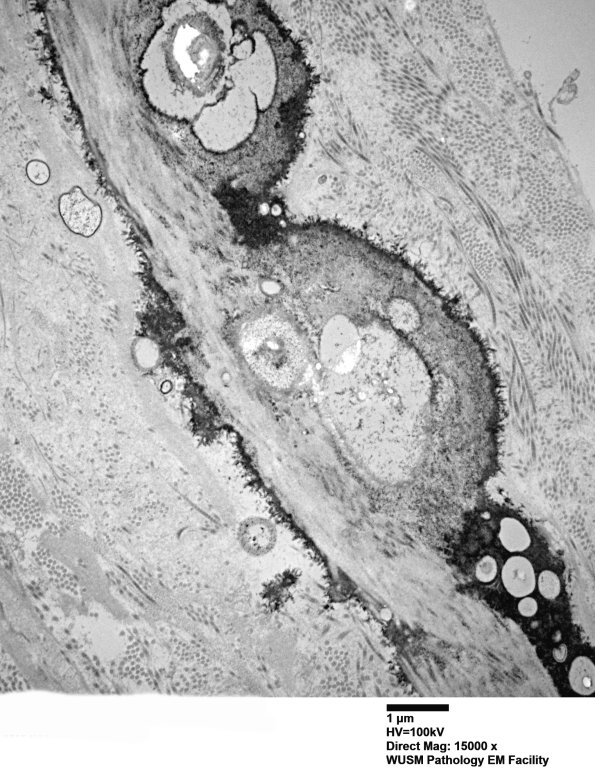

Additional images of perineurial calcification. Perineurial calcifications can be seen in normal individuals as a function of age and as a nonspecific feature of peripheral neuropathies. (electron micrographs)